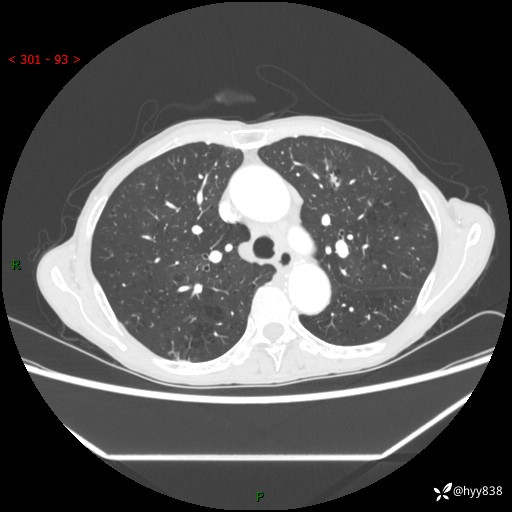

69岁/女,发现肺占位3天余。精彩好病例,请慧诊---(有结果)

【患者信息】:69岁/女

【主诉】:发现肺占位3天余

【现病史及既往史】:患者3天余前因既往肺气肿复查胸部CT发现“右肺下叶结节、双肺多发结节、双肺门及纵膈淋巴结增大”,平素偶有咳白色粘液痰,下肢乏力,无明显低热、盗汗、咯血、胸痛、喘气等不适,今为求明显结节性质遂来我院门诊就诊,门诊以“孤立性肺结节”收治入院。 起病以来,患者精神饮食睡眠一般,大小便正常,体力无明细变化,体重近年来较前下降。

【检查】:胸部CT增强